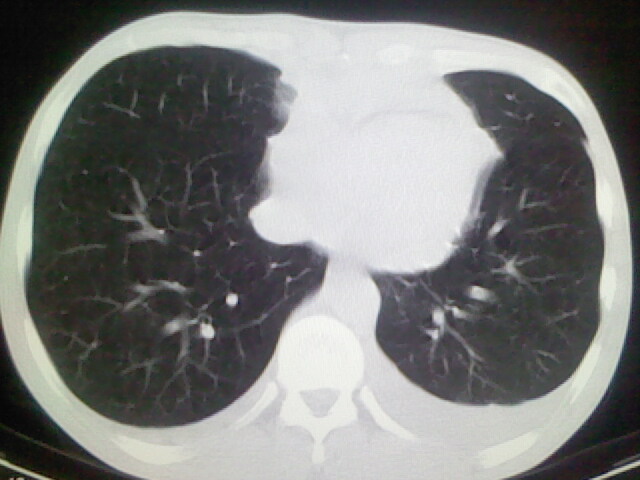

以下是引用杀毒软件在2008-9-3 6:11:00的发言:[br]侵袭性胸腺瘤------一般不侵到气管旁[br][br]考虑----纵隔淋巴瘤,心包及胸膜受累

以下是引用随光逐影在2008-9-3 7:07:00的发言:[br]1)考虑淋巴瘤可能。2)双侧胸腔积液(以左侧为甚)。3)心包积液。